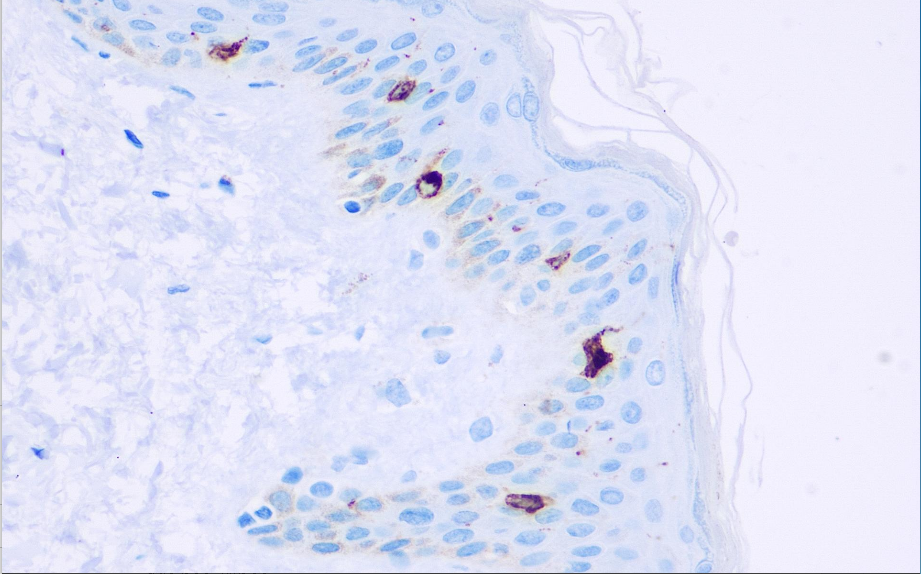

Positive control: Thymus/Skin (Langerhans cells)

Langerin is a type II transmembrane C-type lectin that can be used to assist or replace CD1a in the research of Langerhans cell histiocytosis, especially in the case of Langerhans cell histiocytosis but lacking CD1a expression. The expression of Langerin is valuable for the research. Antibody combinations CD1a, langerin, CD21, CD23, CD35 and S100 are used to distinguish Langerhans cell histiocytosis, histiocytosarcoma, dendritic cell sarcoma, follicular dendritic cell sarcoma and diffuse granuloma. It is of great significance for Rosai-Dorfman disease (sinus histiocytosis with giant lymphadenopathy).

The Langerin antibody reagent can specifically bind to the Langerin antigen. The immunohistochemical kit containing the Langerin antibody reagent is suitable for the precise diagnosis of Langerhans histiocytosis and Langerhans sarcoma.